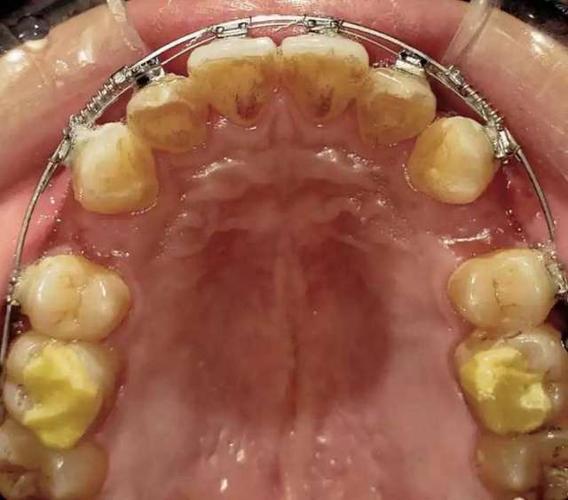

| 真实案例可视化 | 不同年龄(儿童、青少年、成人)、不同错颌畸形的矫正案例,从初诊检查、方案设计到矫正结束的全过程记录,包含患者前后对比图及视频 | 通过真实案例增强说服力,让观众直观了解矫正效果与周期,消除对“矫正效果”的疑虑 |

| 日常护理实操指导 | 矫正期间的刷牙方法(如巴氏刷牙法+牙间刷使用)、牙套清洁技巧(隐形矫正的 aligner 清洗、托槽周边食物残渣清除)、饮食禁忌(硬黏食物避免清单) | 解决矫正人群的日常护理痛点,降低矫正期间口腔问题(如龋齿、牙周炎)的发生风险 |